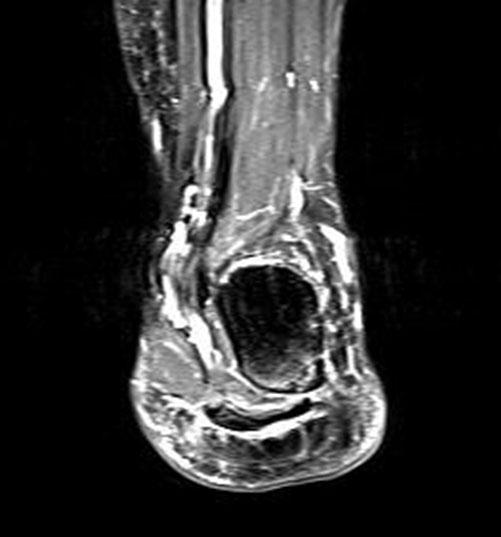

Hier befindet sich ca. 3-5 cm proximal des Tuber calcanei ein als „kritische Zone“ benannter Bezirk, der durch eine ungünstige arterielle Blutzufuhr gekennzeichnet ist (letzte Wiese). Hier finden sich häufig spindelförmige Schwellungen, die bei MRT-Diagnostik nicht selten partielle Nekrosen und Partialrupturen der Achillessehne aufweisen (Abb. 14).

Unabhängig davon können insbesondere chronische Insertionstendinosen der Achillessehne von Partialrupturen (Abb. 15) und erosiven Läsionen des dorsalen Fersenbeines begleitet sein.

Die sonographische Diagnostik eignet sich primär zur Erkennung schmerzhafter Prozesse im Verlauf der Achillessehne und kann bei Bedarf durch Röntgen bzw. MRT ergänzt werden. Besonders bei längeren Verläufen und kräftigen spindelförmigen Schwellungen (>9mm, Normwert <5mm) im Bereich der kritischen Zone sollte ein MRT zum Ausschluss von Nekrosezonen und Partialrupturen vor Therapiebeginn veranlasst werden. Die sonographisch leicht zu erfassende Veränderung der Sehnendicke im mittleren Sehnenanteil ist ein guter Indikator für die Schwere der Erkrankung und die Beurteilung des Behandlungsverlaufes. Die sichtbaren Veränderungen am distalen knöchernen Ansatz der Sehne sind diskreter.

Insbesondere bei größeren Partialrupturen (Abb. 14) sollten operative Verfahren erörtert werden. Kleinere Partialrupturen sind der ESWT gut zugänglich, wie die beiden nachfolgenden Beispiele zeigen: